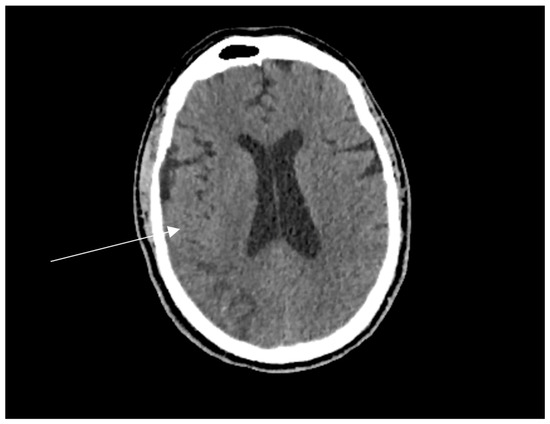

Follow-up contrast-enhanced MRI confirmed stable bilateral parietal infarcts with no evidence of new lesions (Figure 3).

Figure 3. Fluid-attenuated inversion recovery (FLAIR) MRI images showing extensive bilateral parietal ischaemic infarcts, with haemorrhagic transformation (red arrows), confirming the chronicity and bilateral nature of the lesions.